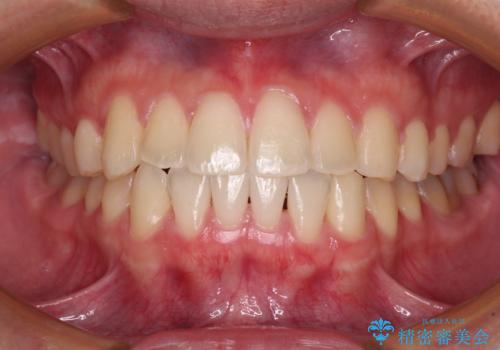

30代女性 前歯のがたつき